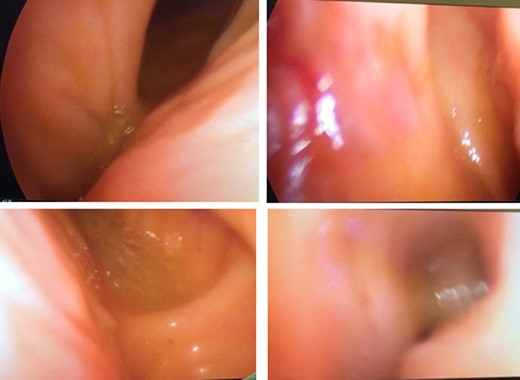

An isolation of the peritoneal cavity with compresses was initially performed. A cross-section of the peripheral truncation was performed on the colonic tape at the point where the ileocolonic anastomosis would be later created. A 10 mm laparoscopic port was inserted in the hole and CO2 insufflations started (Fig. 1). After bowel dilatation the camera was inserted through the laparoscopic port in the colon lumen. During the time the camera is intraluminal, water injection is provided, to avoid thermal injury of the mucosa. Overview of the lumen, until the splenic flexure bend and the beginning of the descending colon was performed. A hole was then applied to the colic tape at the lower third of the sigmoid (Fig. 2). Again, a 10 mm laparoscopic port was inserted and the laparoscopic camera was used to inspect the bowel lumen up to the splenic flexure. After the endoscopic inspection of the bowel has been completed, the laparoscopic ports were withdrawn (Fig. 3). The holes were converged with seromuscular stitches of the sigmoid and omentumplasty. A stapled side to side anastomosis was hen performed between terminal ileum and colon. The patient discharge hospital without any complication on the eighth postoperative day. The histopathology of the specimen shows low grade adenocarcinoma of the colon, pT4bN1b.

Intraluminal view of the colon through the laparoscopic video camera.